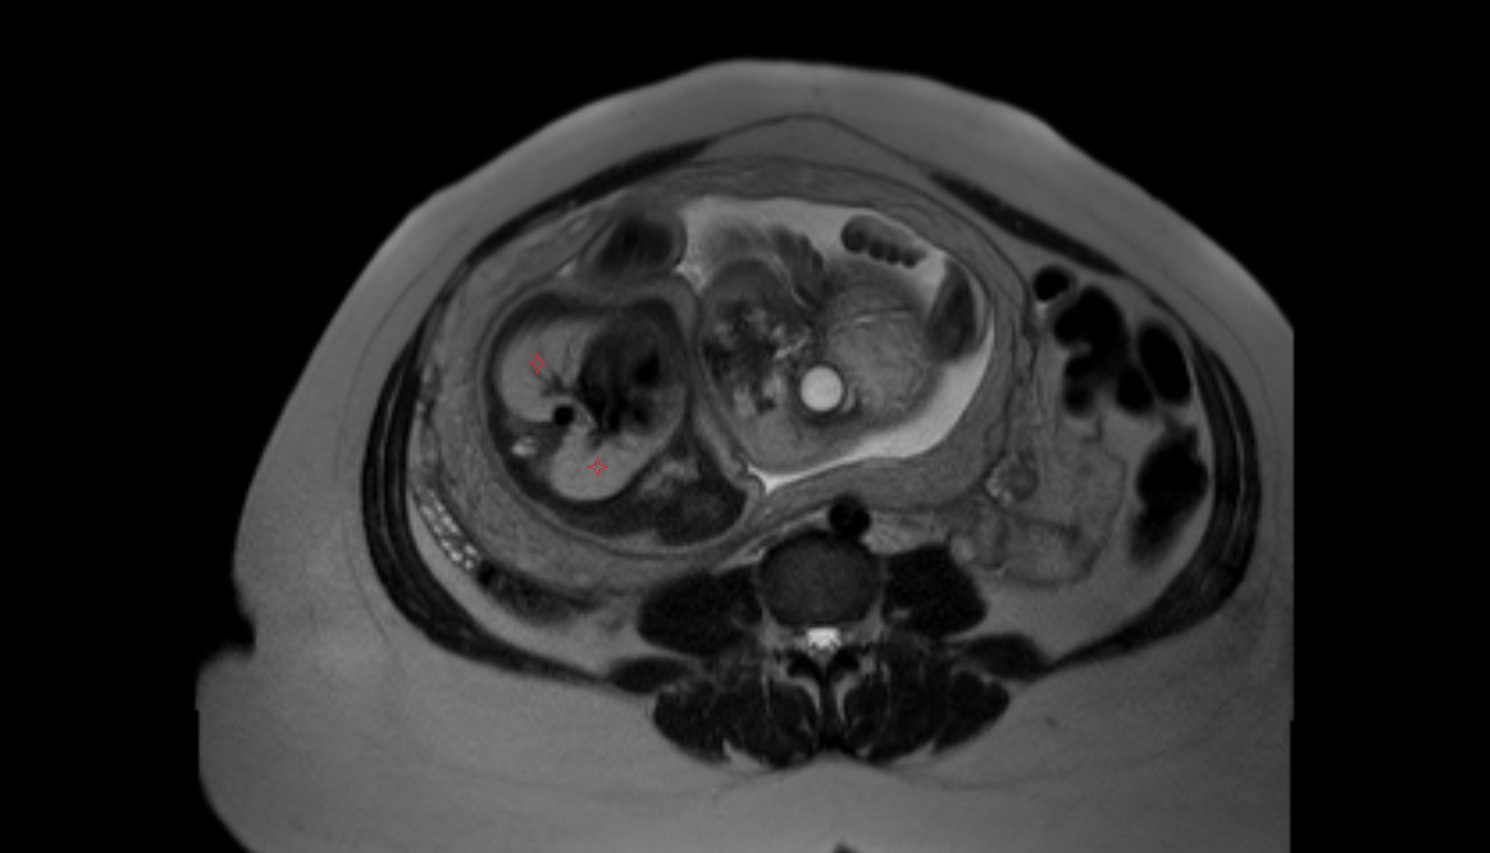

- Placenta

- Uterus (pregnancy)

- Amniotic fluid

- Umbilical cord

- Urinary Bladder in Pregnancy

- Fetal brain

- Fetal caudate nucleus

- Fetal thalamus

- Fetal cerebellum

- Fetal lateral ventricle

- Fetal kidneys